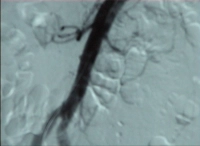

Video clip: SMA occlusion close to its origin with occlusion of the celiac trunk